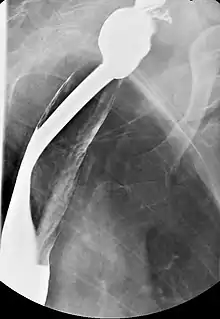

Serial contrasted gastrointestinal radiography or upper-gastrointestinal endoscopy may reveal the web in the esophagus. Blood tests demonstrate a hypochromic microcytic anemia that is consistent with an iron-deficiency anemia. Biopsy of involved mucosa typically reveals epithelial atrophy (shrinking) and varying amounts of submucosal chronic inflammation. Epithelial atypia or dysplasia may be present. It may also present as a post-cricoid malignancy which can be detected by loss of laryngeal crepitus. Laryngeal crepitus is found normally and is produced because the cricoid cartilage rubs against the vertebrae.

Barium esophagography and videofluoroscopy will help to detect esophageal webs. Esophagogastroduodenoscopy will enable visual confirmation of esophageal webs. The webs occur due to sub-epithelial fibrosis.